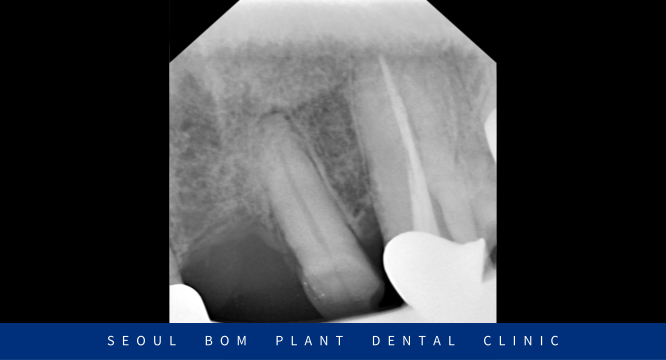

보철 치료시 보철물 내부의 치아가 너무 약하거나 짧으면

유지력이 떨어질 수밖에 없기 때문에

신경치료를 마무리한 뒤 코아 레진을 이용하여 파절된 치아머리 부분을

단단하게 채워주는 작업을 진행한 뒤 최종 보철물 제작을 위해

필요한 만큼 소량으로 치아 다듬기를 진행하였습니다.